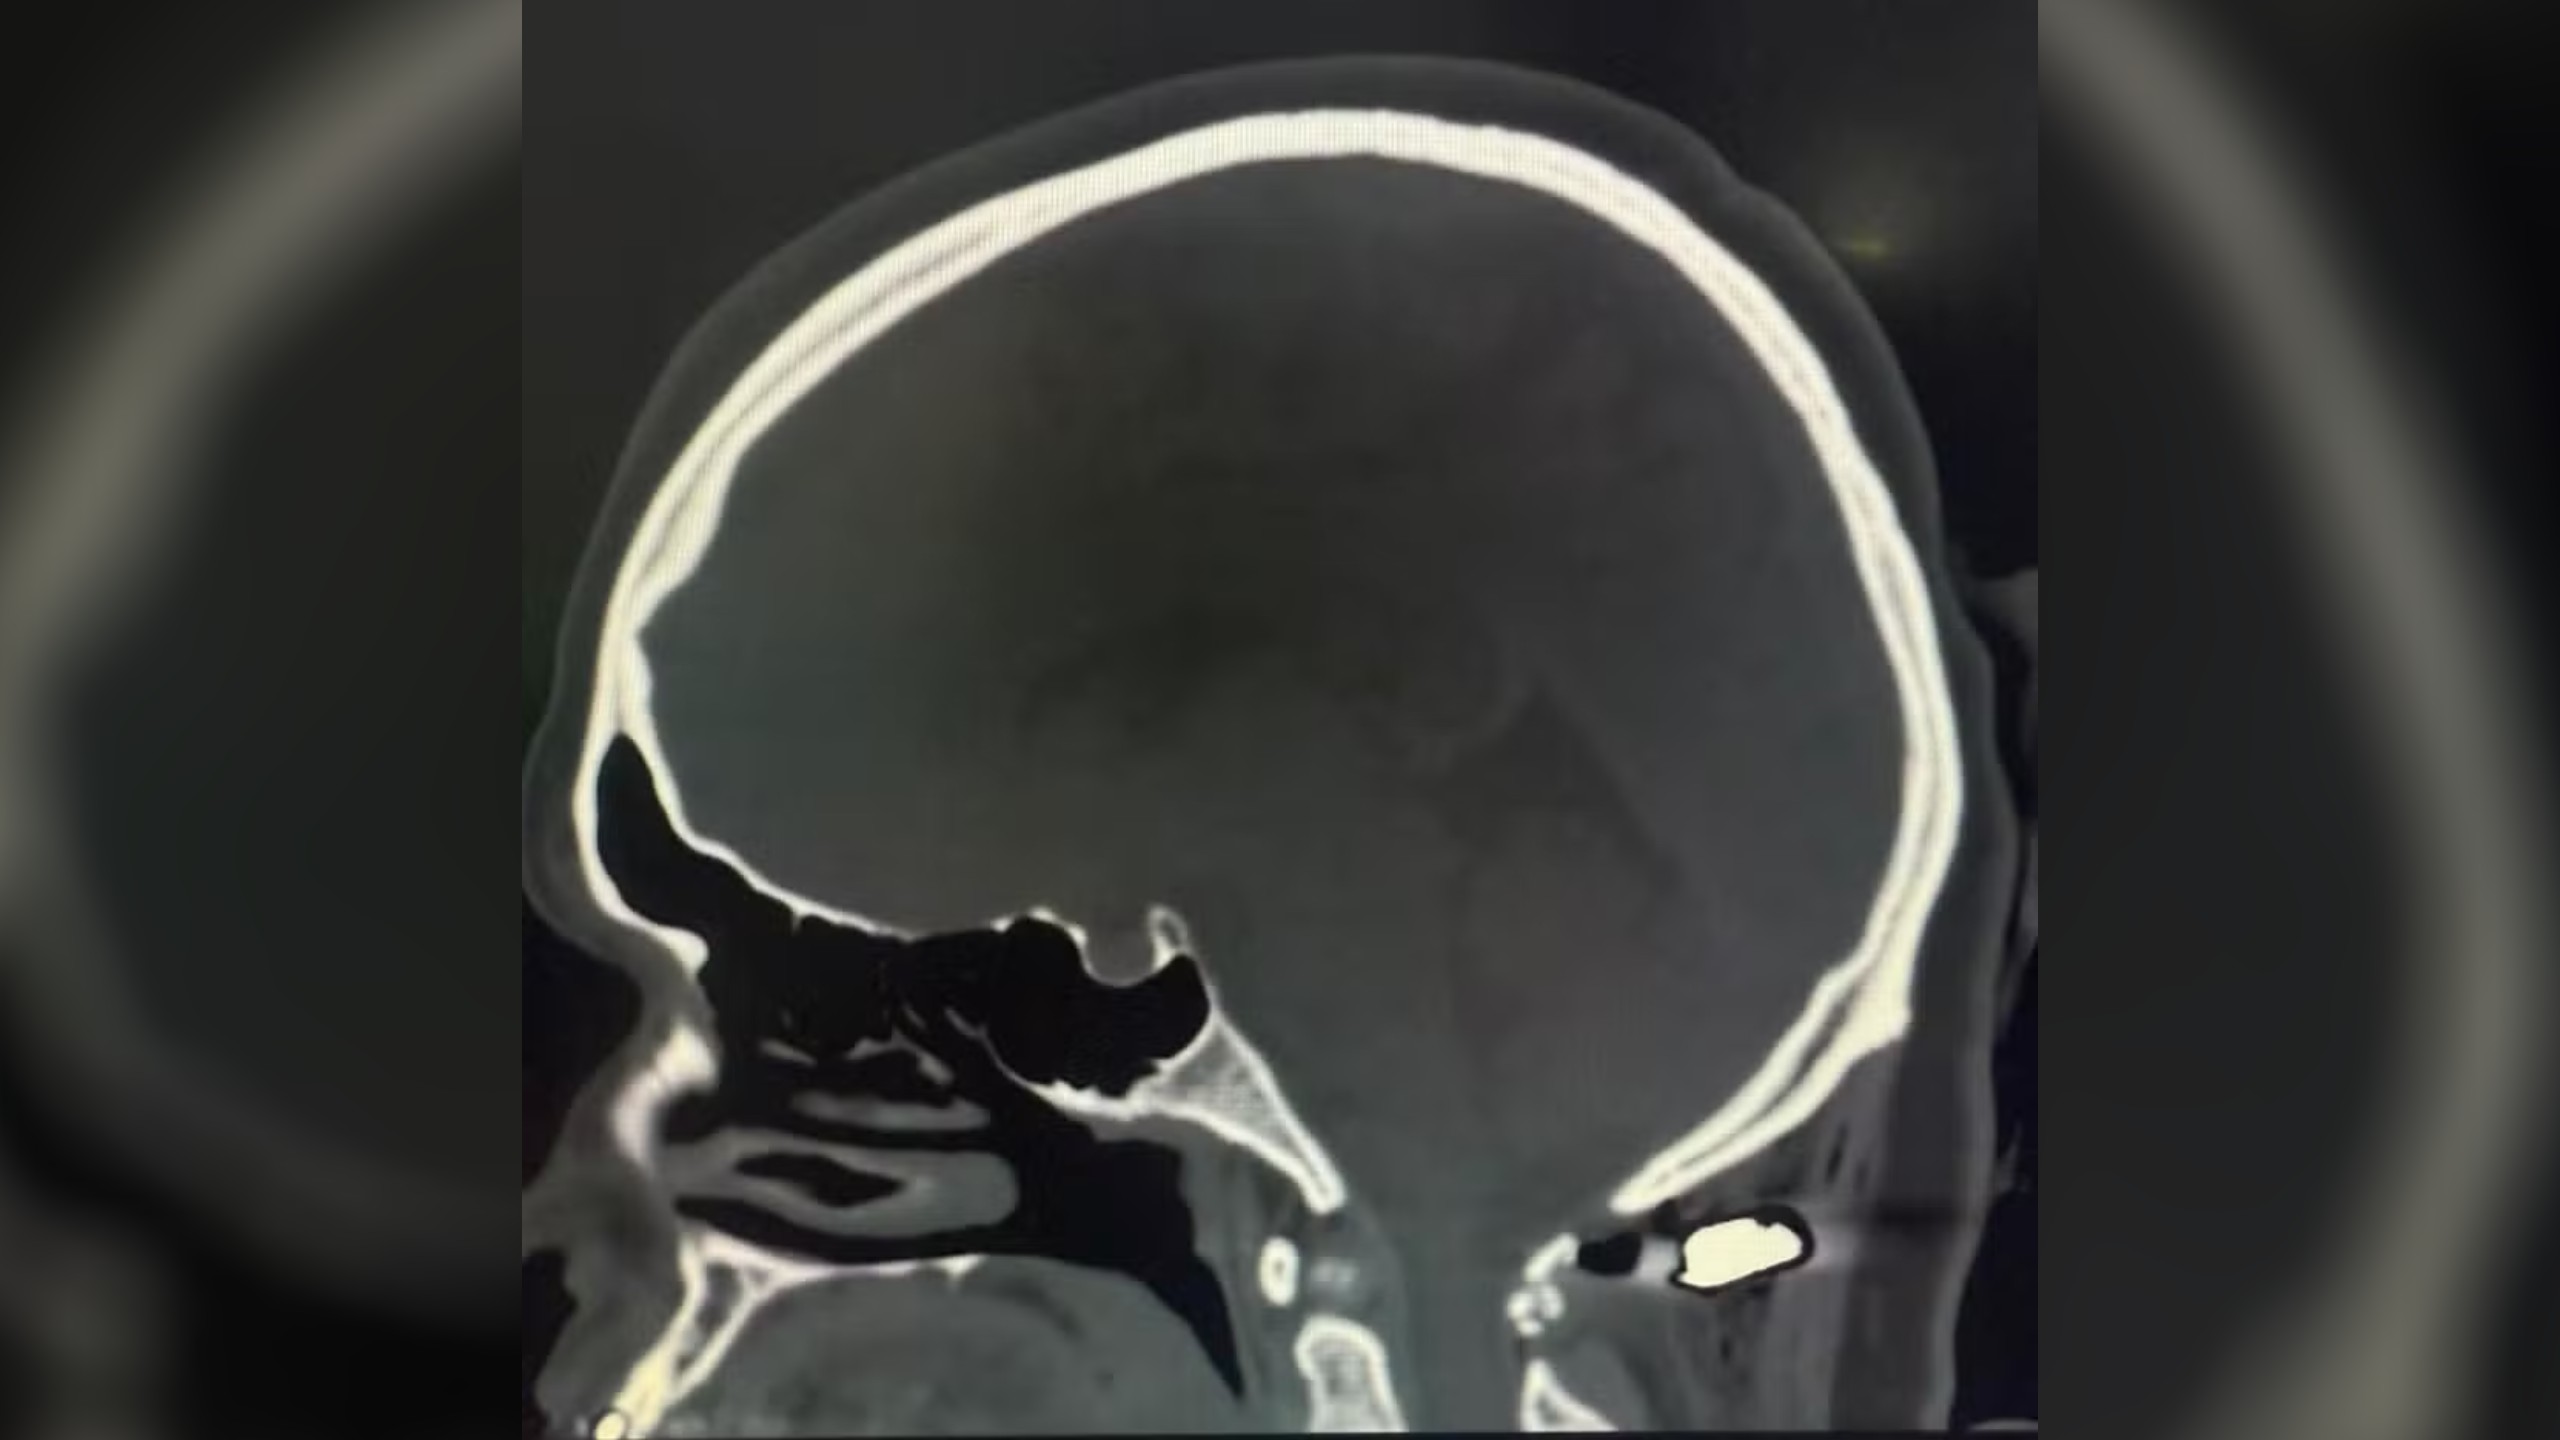

Tomografia mostra bala alojada a 4 milímetros da medula cervical de Juliete. — Foto: Hospital Angelina Caron / Divulgação

Tomografia mostra bala alojada a 4 milímetros da medula cervical de Juliete. — Foto: Hospital Angelina Caron / Divulgação Uma mulher de 36 anos foi baleada na nuca durante um tiroteio em uma distribuidora de bebidas no bairro Guaraituba, em Colombo, na Região Metropolitana de Curitiba, na tarde de sábado (19). A vítima, identificada como Juliete Pires dos Santos Scrok, estava em um carro com o marido e a filha quando foi atingida por uma bala perdida. Segundo a Polícia Civil do Paraná (PC-PR), Juliete não era o alvo dos disparos.

“Quando vimos a tomografia, eu tive a curiosidade de medir a distância do projétil até a medula cervical. Deu apenas quatro milímetros. Uma lesão ali poderia causar morte ou tetraplegia. É inacreditável que ela esteja tão bem — foi realmente um milagre”, relatou o médico.